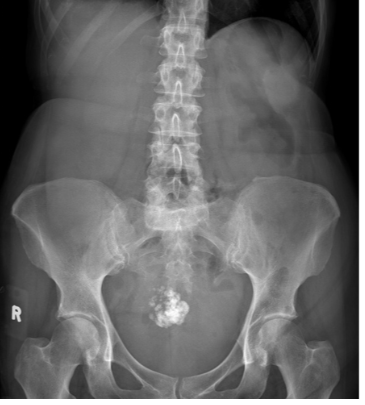

What is the cause of the abnormal calcification?

Staghorn renal calculus